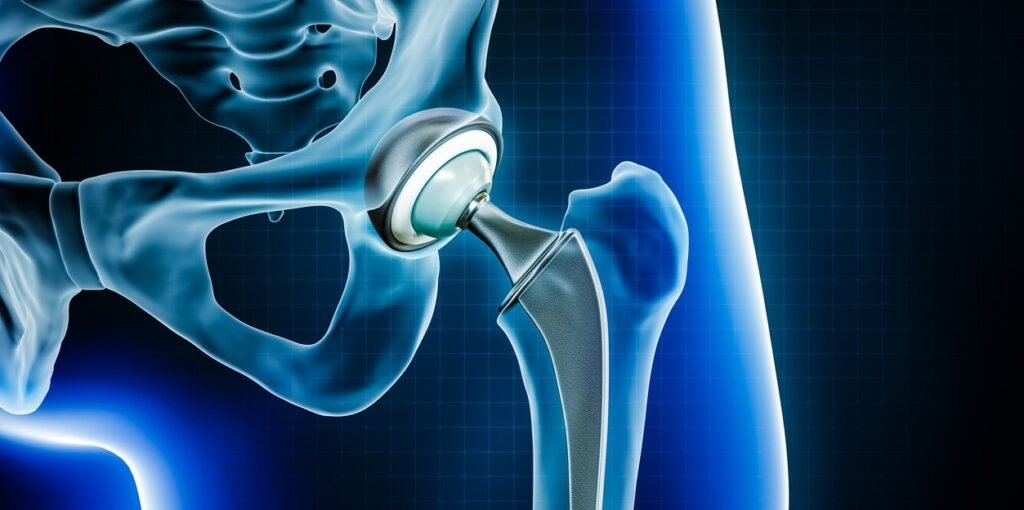

Kidney Transplant

Kidney transplant is one of the most commonly performed procedures in India. It is recommended for patients with chronic kidney disease or kidney failure who are dependent on dialysis.